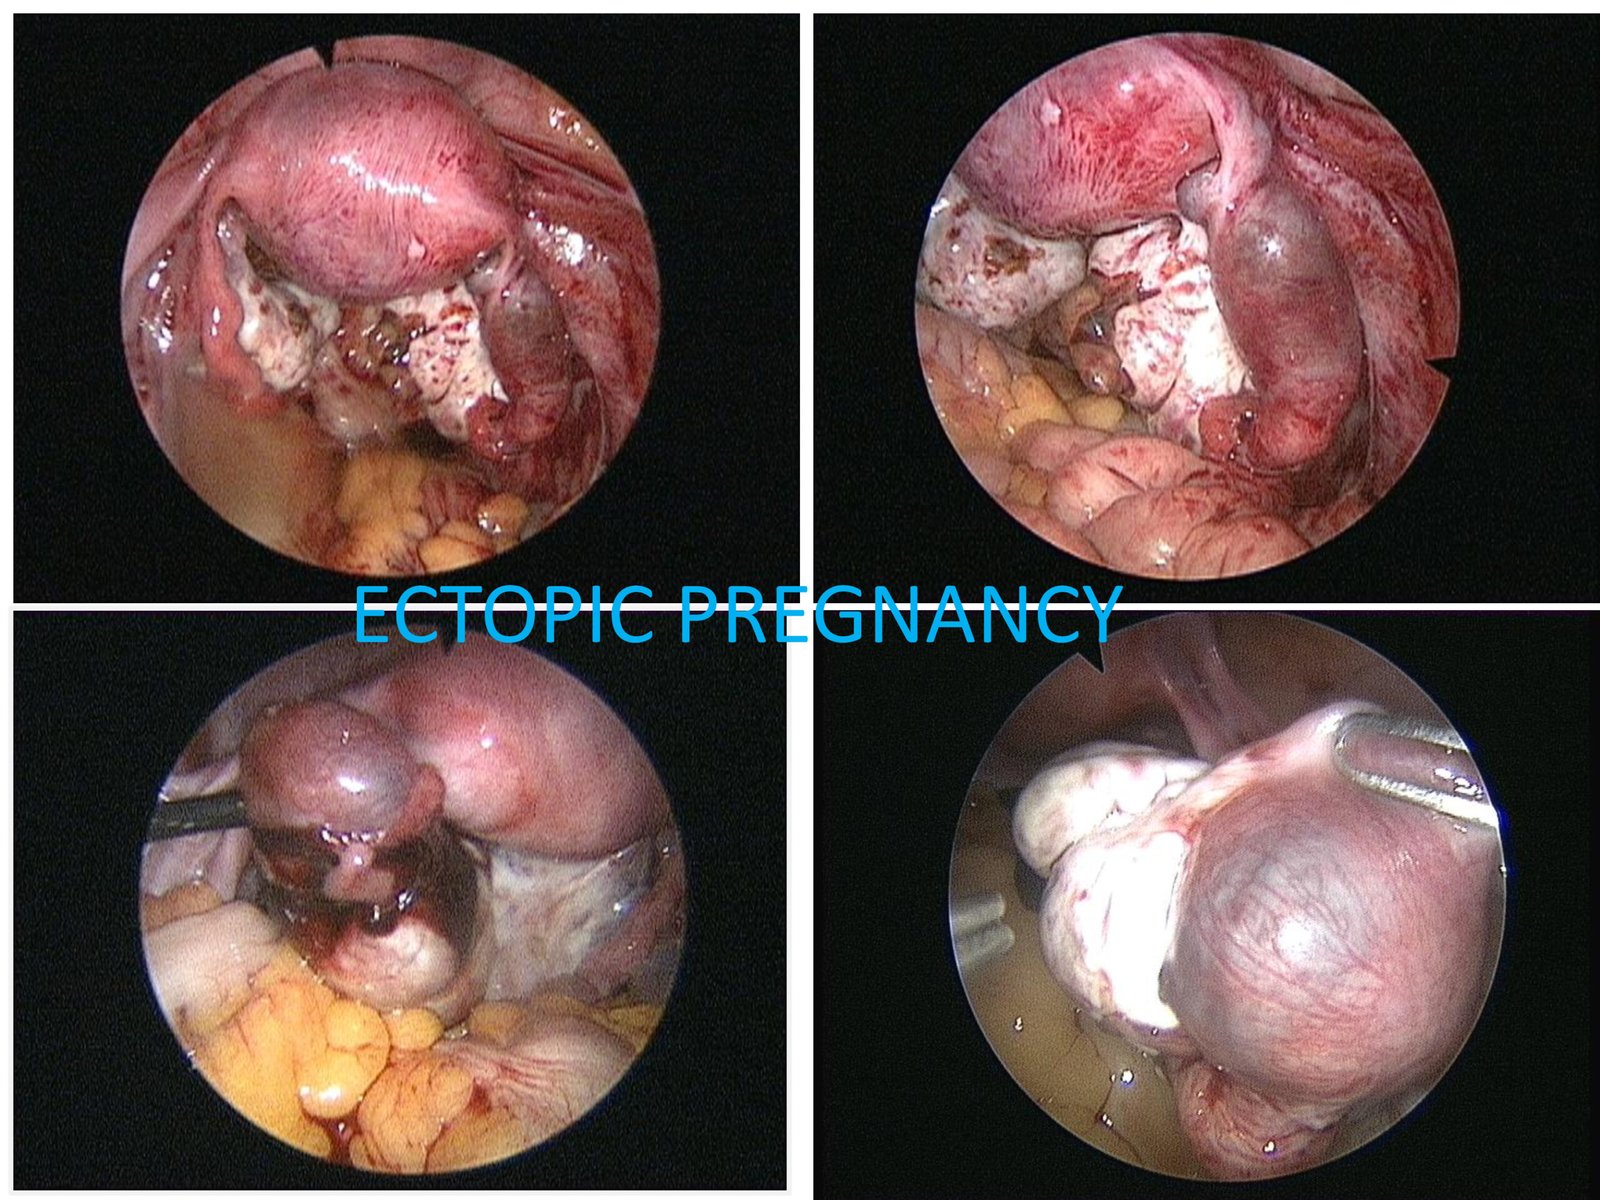

The diagnosis is also confirmed with ultrasound and blood flow studies (Doppler) during which the sac may be visualized in the region of the adnexa close to ovary. The treatment may be medical with methotrexate (chemotherapeutic agent) given either as oral medication or an injectable, depending on the combined laboratory and clinical findings. If surgical intervention is decided upon then laparoscopic surgery will be performed in most patients who are hemodynamically stable. In cases where the patient presents late with the symptoms or the pregnancy has ruptured with bleeding into the abdomen laparotomy (10%) is performed.

The affected tube is most often if not always removed after examining the opposite tube and assessing the patient’s chances of future conception. Even with one healthy tube it is possible to conceive. In our experience removal of tube almost always reduced chances of recurrence and helped improve pregnancy rates by either trying for conception with the opposite tube or with ART.